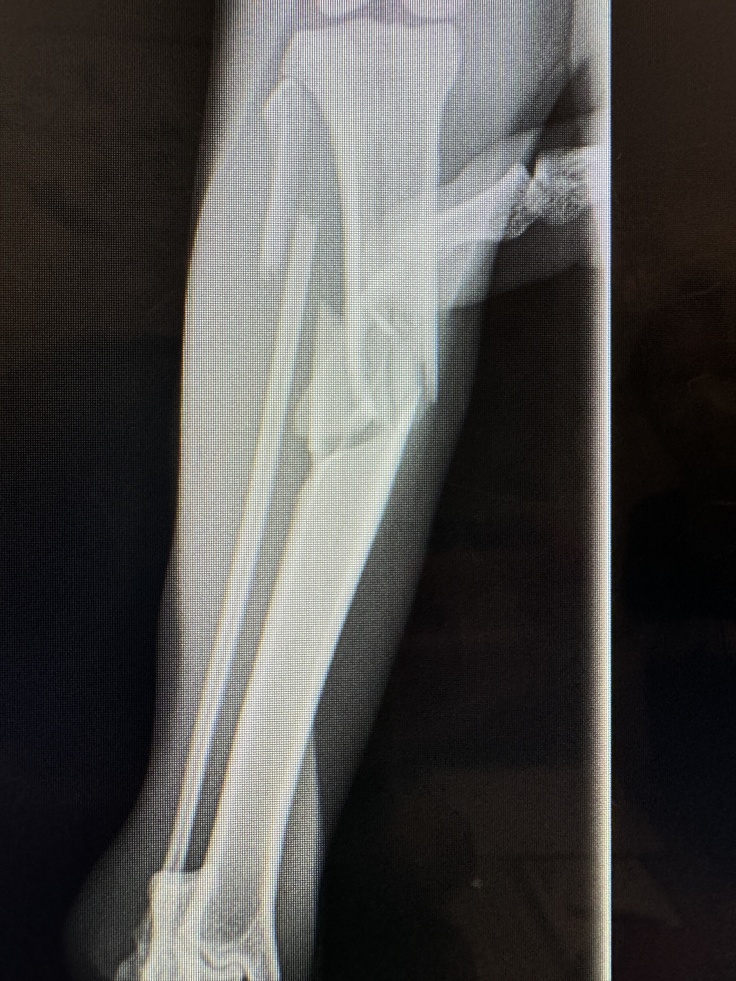

下にいる猫は3階からおちて道にうずくまっているところを保護されました

胸を強打していて肺気腫

さらに、横隔膜破裂による心嚢ヘルニア

心臓の横に肝臓がある・・・そんな状況です

そして、2箇所の骨折